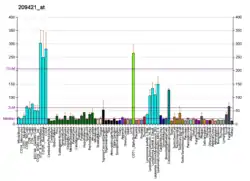

Reductions in expression of DNA repair genes (usually caused by epigenetic alterations) are very common in cancers, and are ordinarily much more frequent than mutational defects in DNA repair genes in cancers. (See Frequencies of epimutations in DNA repair genes.) In a study of MSH2 in non-small cell lung cancer (NSCLC), no mutations were found while 29% of NSCLC had epigenetic reduction of MSH2 expression.[39] In acute lymphoblastoid leukemia (ALL), no MSH2 mutations were found[40] while 43% of ALL patients showed MSH2 promoter methylation and 86% of relapsed ALL patients had MSH2 promoter methylation.[41] There were, however, mutations in four other genes in ALL patients that destabilized the MSH2 protein, and these were defective in 11% of children with ALL and 16% of adults with this cancer.[40]

Methylation of the promoter region of the MSH2 gene is correlated with the lack of expression of the MSH2 protein in esophageal cancer,[42] in non-small-cell lung cancer,[39][43] and in colorectal cancer.[44] These correlations suggest that methylation of the promoter region of the MSH2 gene reduces expression of the MSH2 protein. Such promoter methylation would reduce DNA repair in the four pathways in which MSH2 participates: DNA mismatch repair, transcription-coupled repair[5] homologous recombination,[6][45][46] and base excision repair.[7] Such reductions in repair likely allow excess DNA damage to accumulate and contribute to carcinogenesis.

The frequencies of MSH2 promoter methylation in several different cancers are indicated in the Table.

| Cancer | Frequency of MSH2 promoter methylation | Ref. |

|---|---|---|

| Acute lymphoblastic leukemia | 43% | [41] |

| Relapsed Acute lymphoblastic leukemia | 86% | [41] |

| Renal cell carcinoma | 51–55% | [47][48] |

| Esophageal squamous cell carcinoma | 29–48% | [42][49] |

| Head and neck squamous-cell carcinoma | 27–36% | [50][51][52] |

| Non-small cell lung cancer | 29–34% | [39][43] |

| Hepatocellular carcinoma | 10–29% | [53] |

| Colorectal cancer | 3–24% | [44][54][55][56] |

| Soft-tissue sarcoma | 8% | [57] |